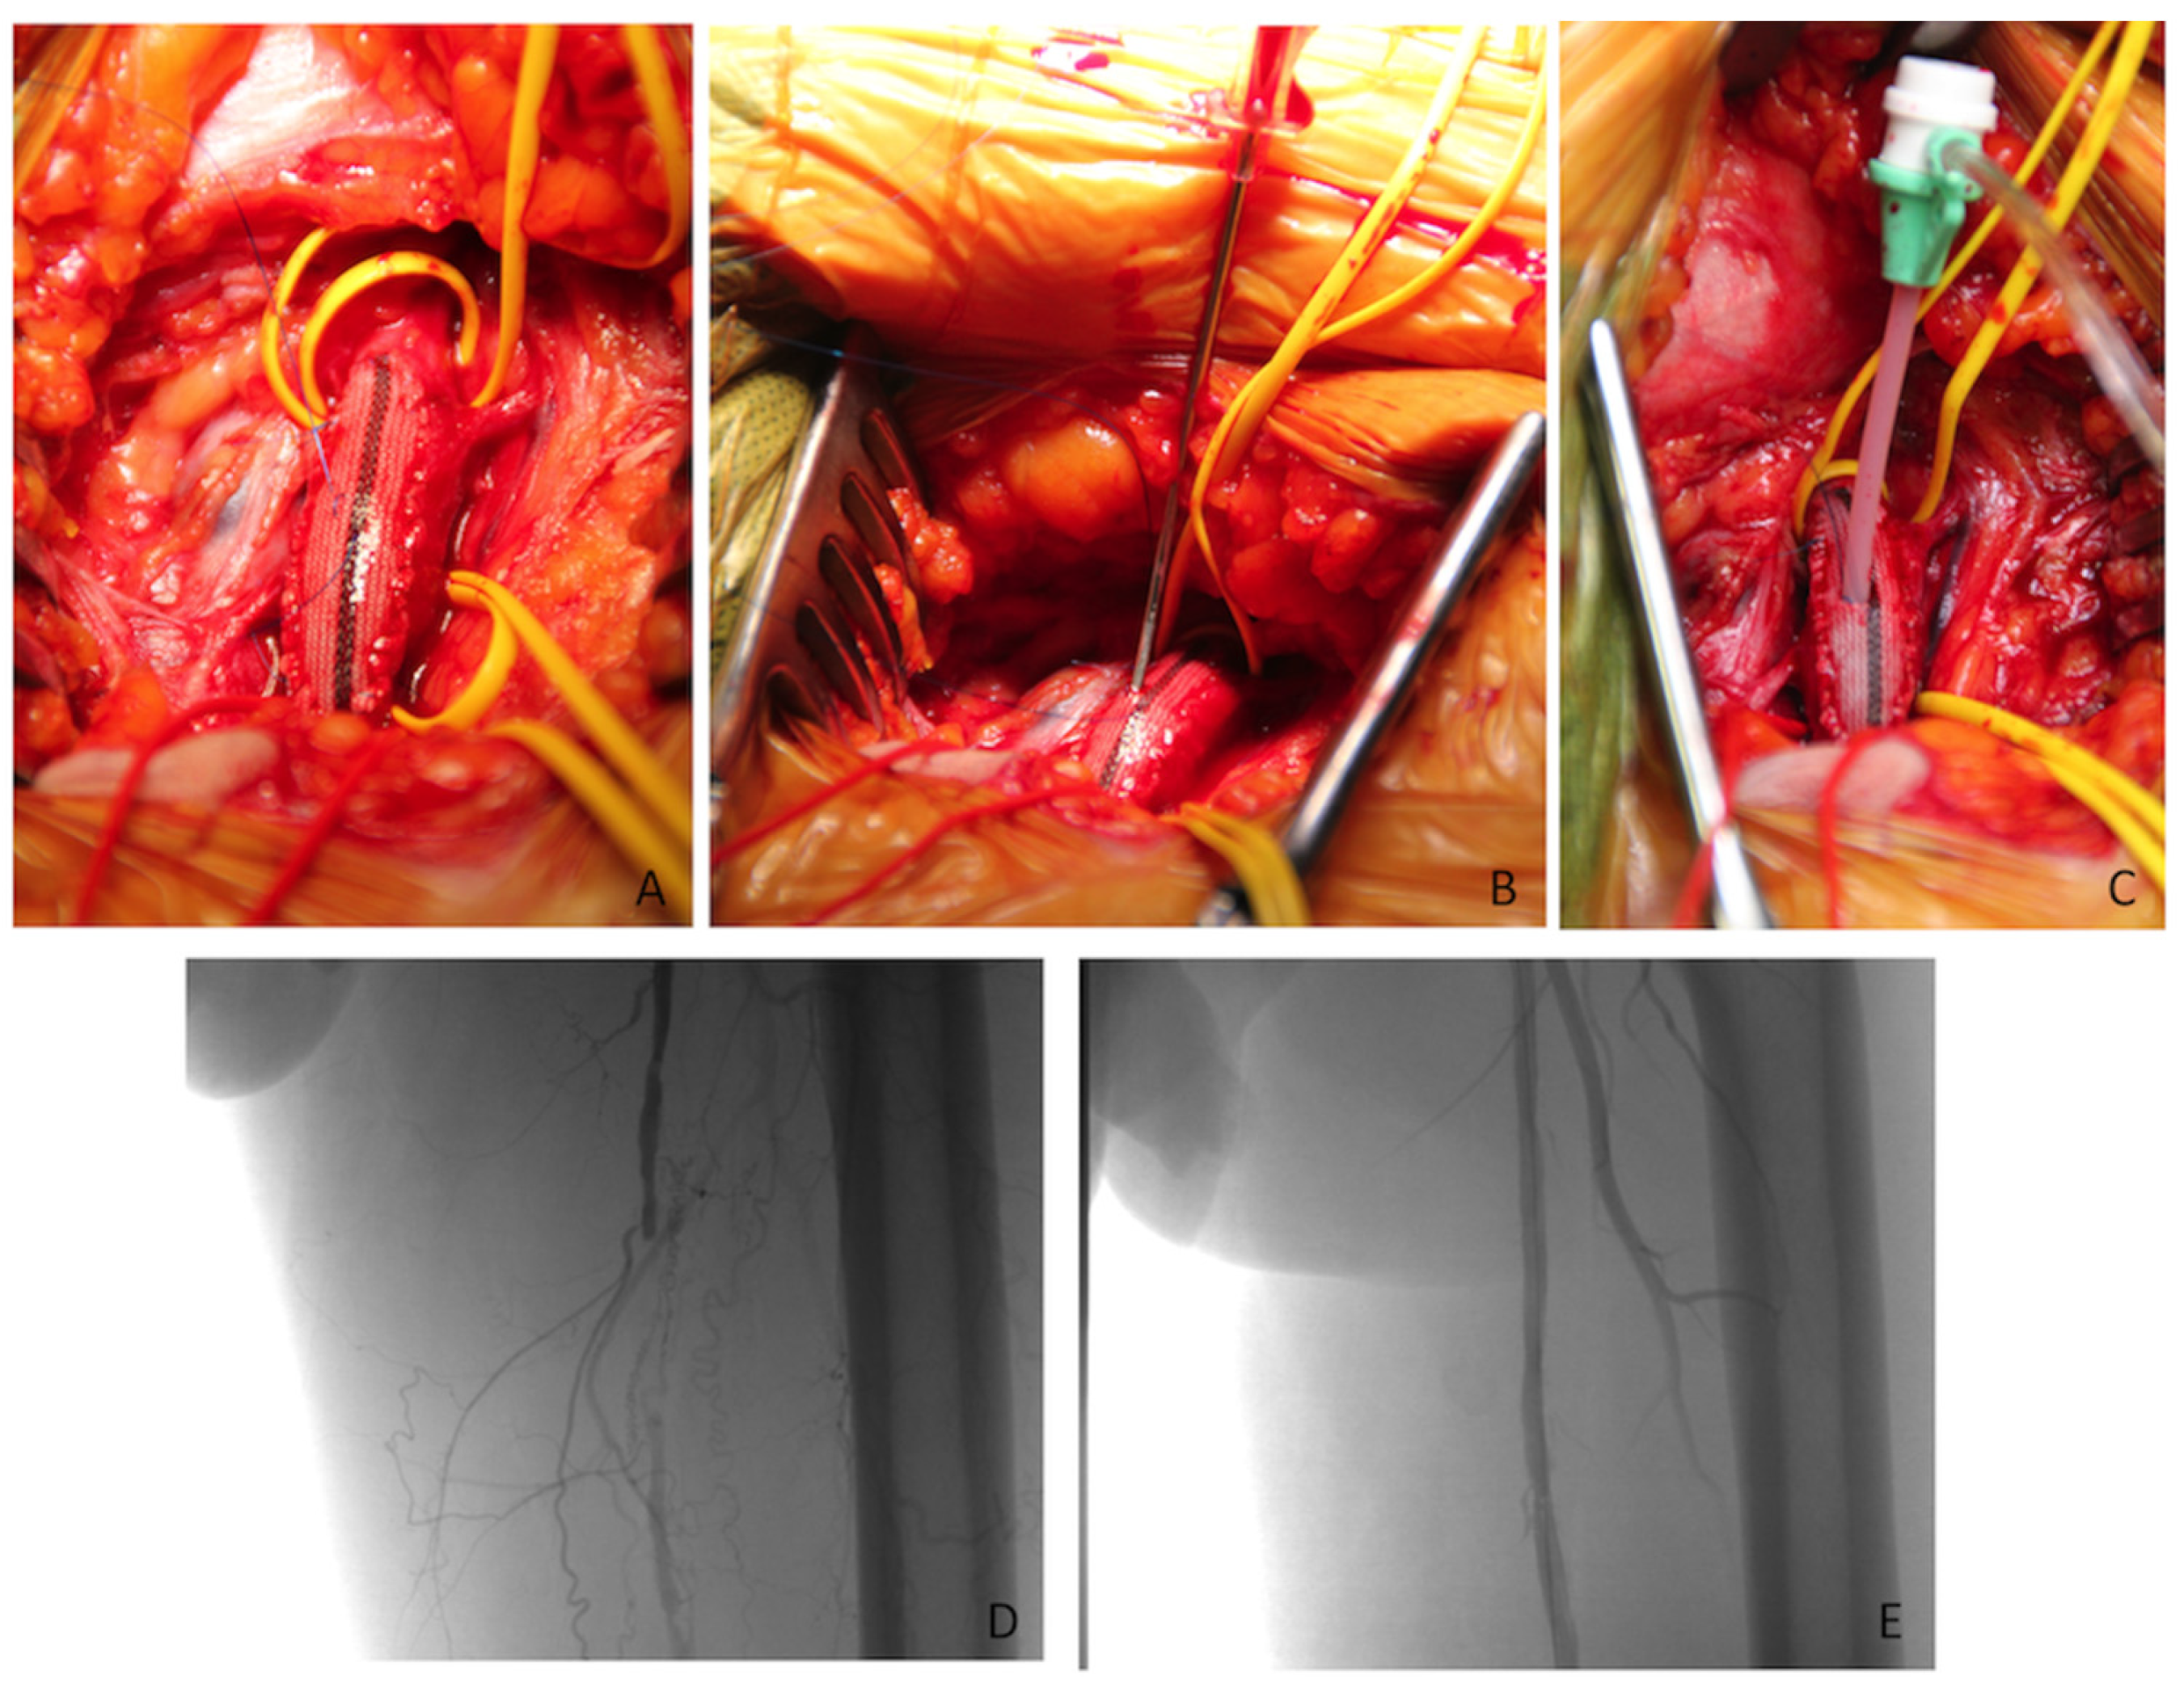

2.1. HT with Femoral Artery Patch Angioplasty and Endovascular Treatment (HT-Patch)

2.2. HT with Endovascular Treatment and Bypass Surgery (HT-Bypass)